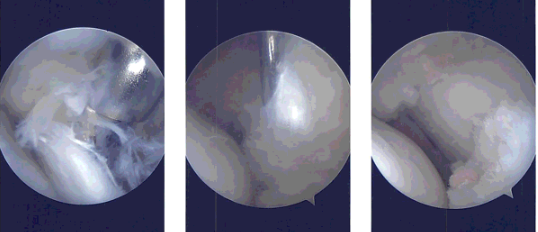

Intraoperative Arthroscopy Images

On examination of the lateral compartment, there was a tear on the anterior horn of the lateral meniscus with part of the root Intact. Incision and debridement of the anterior horn was not taken as the wound was frayed.

Debridement was done using punches as well as shaver. A balanced margin was made. There was no osteochondral lesion on the lateral femoral condyle.

Upon examination of the lateral femoral condyle, there was grade 2 to grade 4 osteochondral lesions over the trochlea and the patella. Debridement of the osteochondral lesion was done using a shaver.

Chondral pick was used to do microfracture on the osseous surface of the patella at two points. The knee was thoroughly irrigated. Examination was again performed from the medial portal and balancing of the lateral meniscus was performed and confirmed.